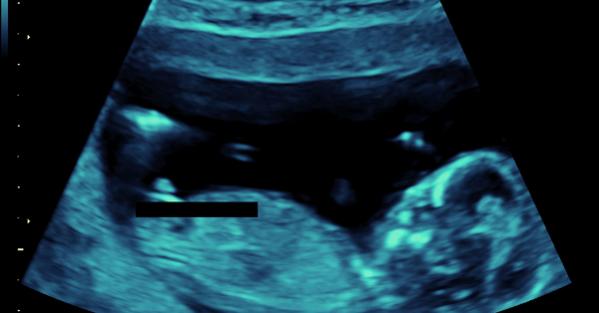

So happy to be posting here! Here are my pics from 13 weeks and 20 weeks...